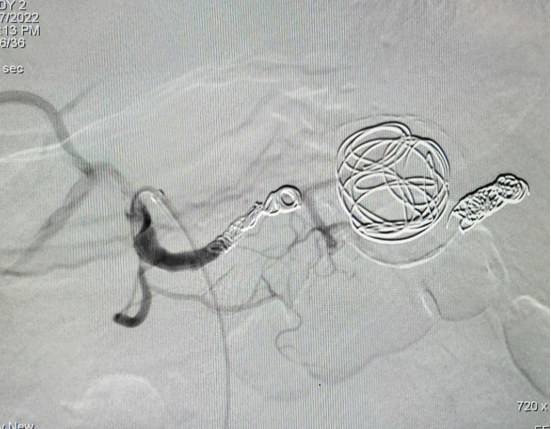

病例5 多发动脉瘤分支+主干栓塞

图为:分支栓塞

图为:主干栓塞最后造影

病例6 脾动脉瘤Viabahn支架隔绝

图为:术后复查